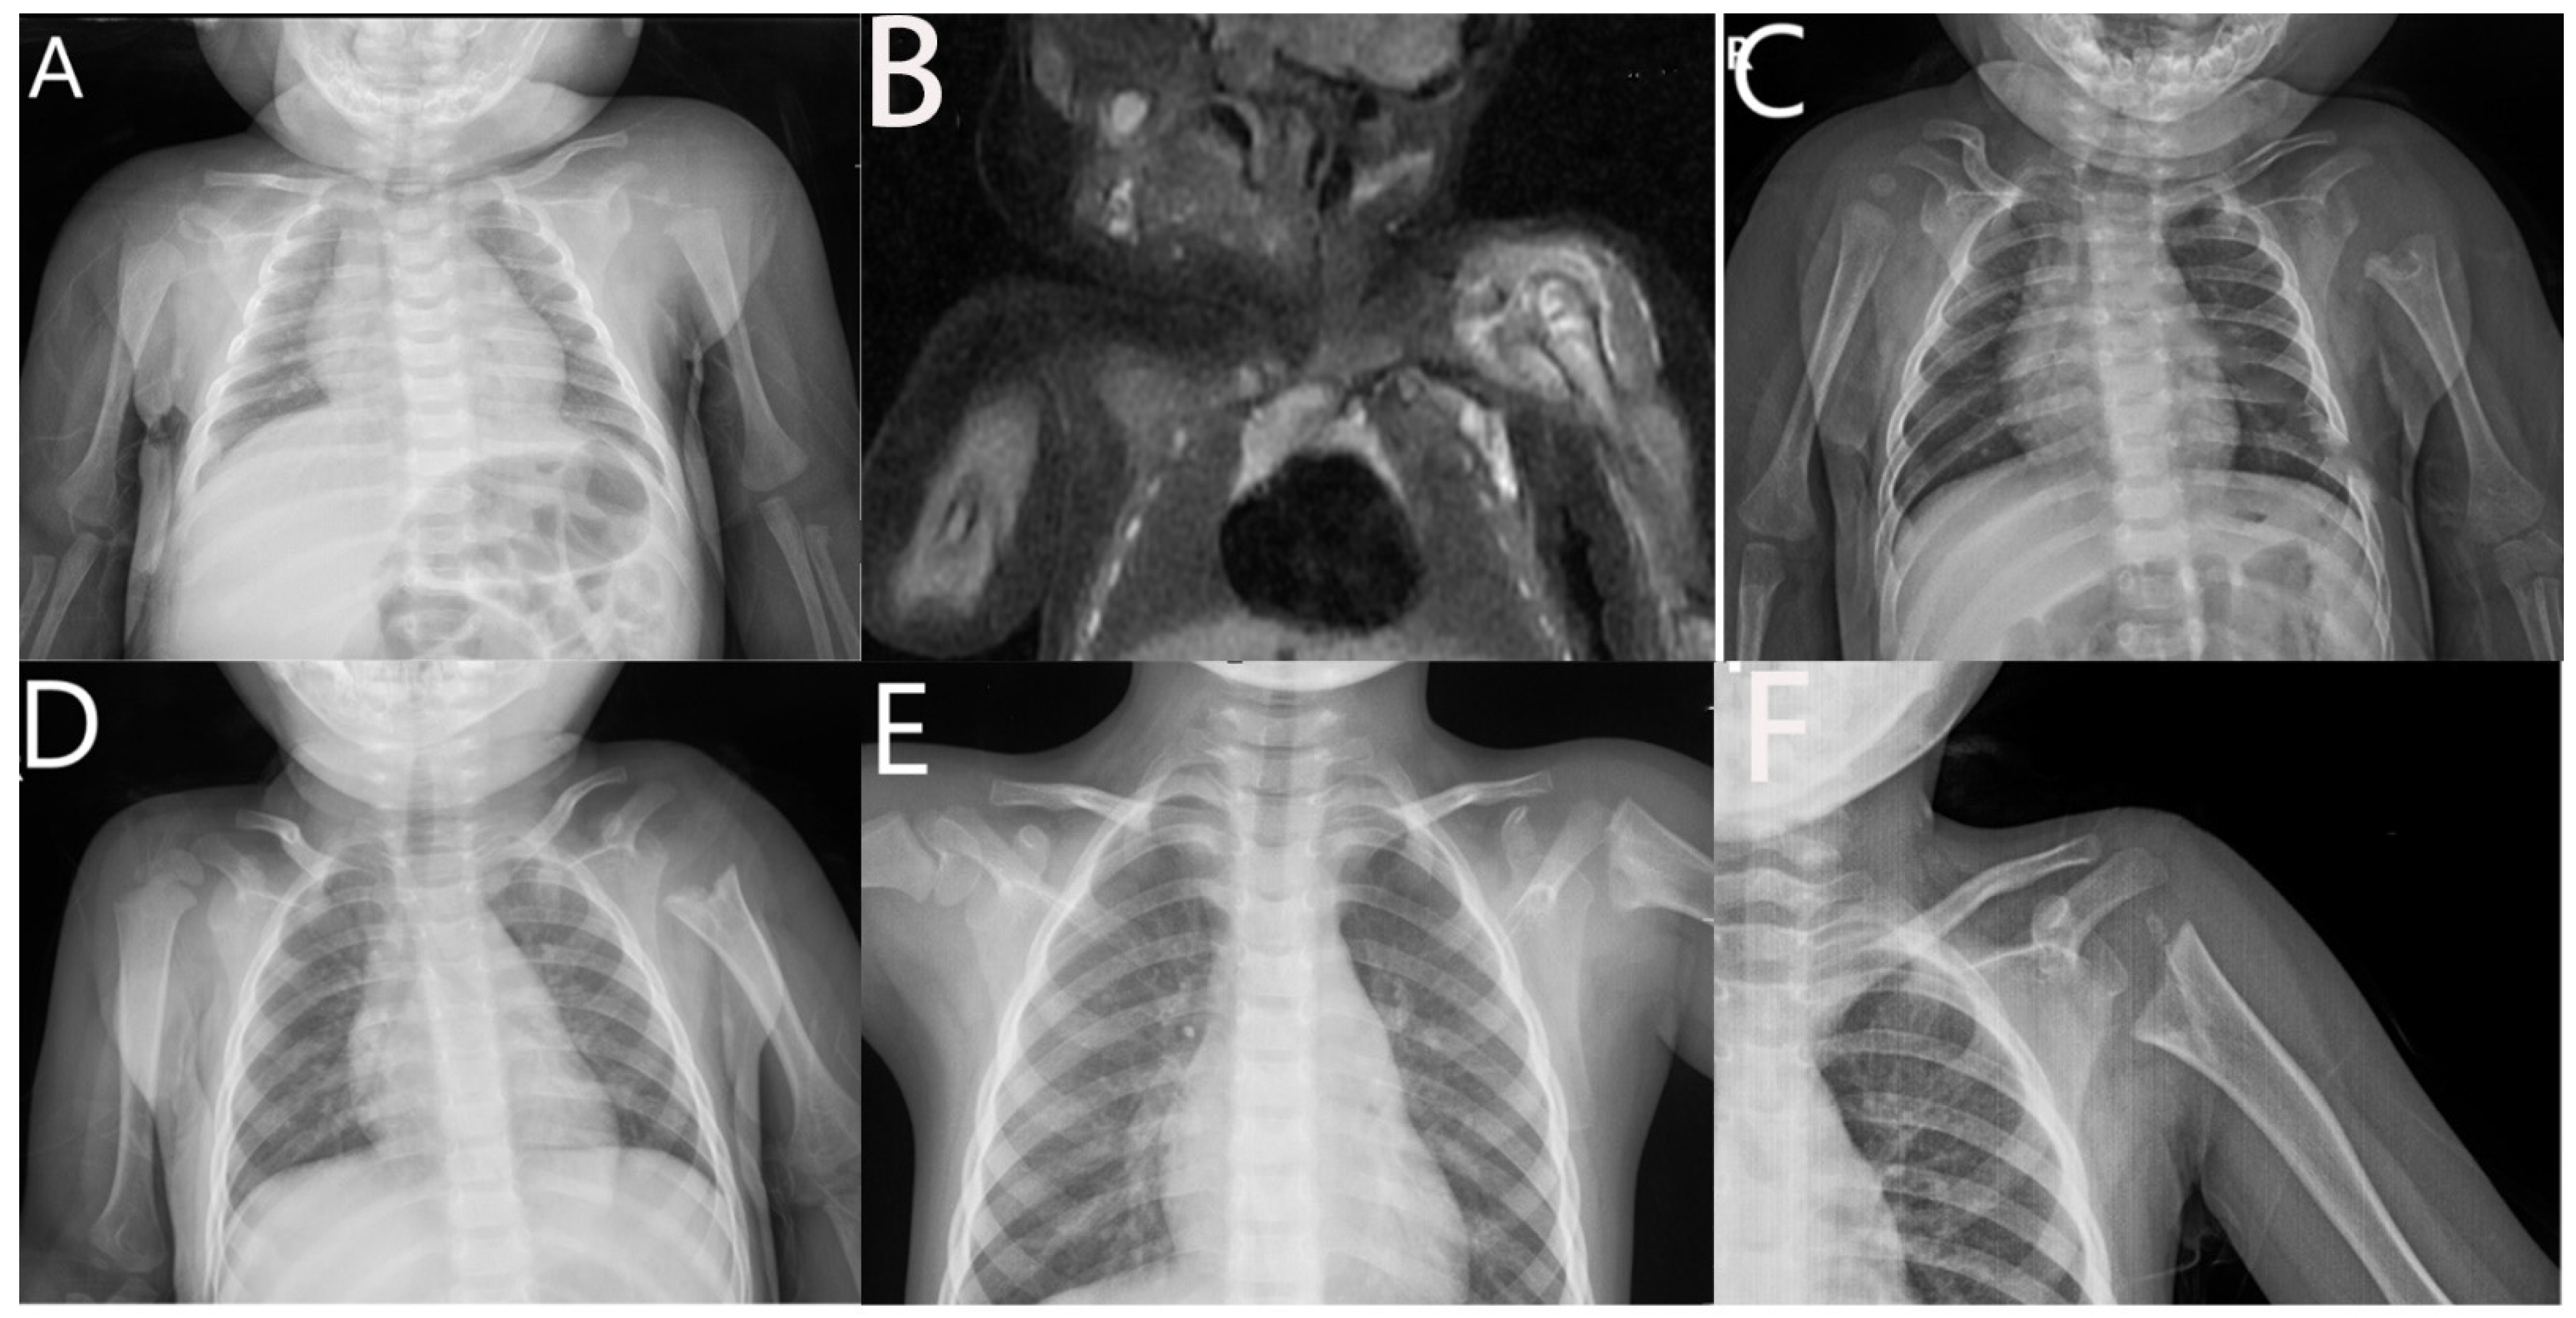

3. Results

4. Discussion

5. Conclusions